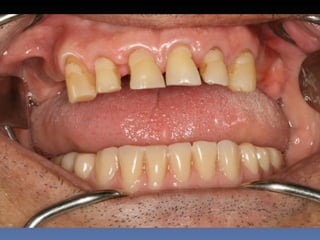

BOX 5

Rute Gomes Mealha

Idade – 70 anos

Sexo – Feminino

Raça – Caucasiana

ASA – I

Data- 24-04-2012

Diagnóstico: Desdentada

mandibular posterior.

Plano de tratamento: Exondontia de todos os dentes

mandibulares existentes, instalação de 5 implantes

endo-ósseos – Protocolo Branemark, com carga

imediata.